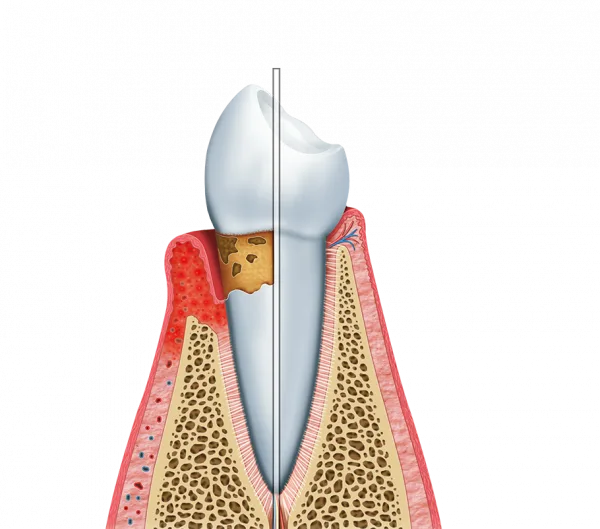

Escolher uma clínica de gengiva em São Paulo pode trazer diversos ganhos para a sua saúde bucal. A Periodontia, especialidade que se concentra no suporte aos tecidos que protegem os dentes, é essencial para prevenir complicações e manter a estabilidade da arcada.

O foco de uma clínica de gengiva em São Paulo é proporcionar um equilíbrio entre saúde e estética. O tratamento adequado dos tecidos moles evita problemas severos, como a mobilidade e a perda dentária, promovendo bem-estar contínuo ao paciente.

A prevenção de doenças periodontais é crucial para evitar quadros como gengivite e periodontite. Clínicas especializadas oferecem diagnósticos precoces que ajudam a interromper o avanço de infecções antes que elas atinjam o suporte ósseo dos dentes.